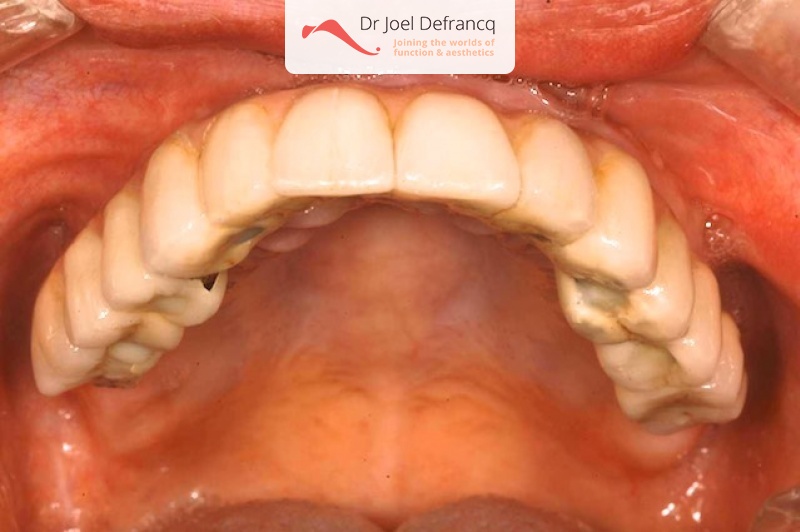

Behandeling tandheelkundige implantaten

- Vaste tanden op implantaten (bovenkaak)